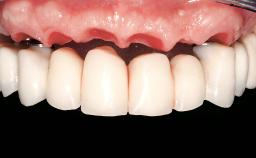

Immediate Loading of Eight Implants in the Maxilla and Six Implants in the Mandible and Final Restoration with Three-Unit and Four-Unit FDPs

Extensive scientific evidence has confirmed that immediately loaded implants with fixed full-arch provisional restorations can osseointegrate with success rates similar to conventionally or delayed loaded implants. A number of immediate-provisionalization techniques for edentulous jaws have been described. Some protocols differ when it comes to prefabricated provisional templates versus complete denture conversion; intrasurgical impressions versus direct relining; and cemented versus screw-retained provisional restorations. In this context, complete-denture conversion has been proposed for either intrasurgical impressions or direct relining. Another possibility is the utilization of a prefabricated provisional to be adapted either in the mouth (by direct relining) or in the laboratory (on a working model obtained from an intrasurgical impression).

Defining Characteristics Fully edentulous upper jaw to be rehabilitated with an implant-borne fixed dental prosthesis

Loading Protocol Immediate